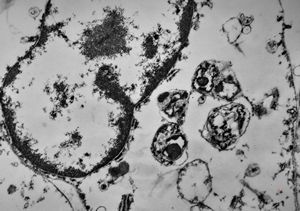

M,10y. | herpes virus - herpetic encephalitis